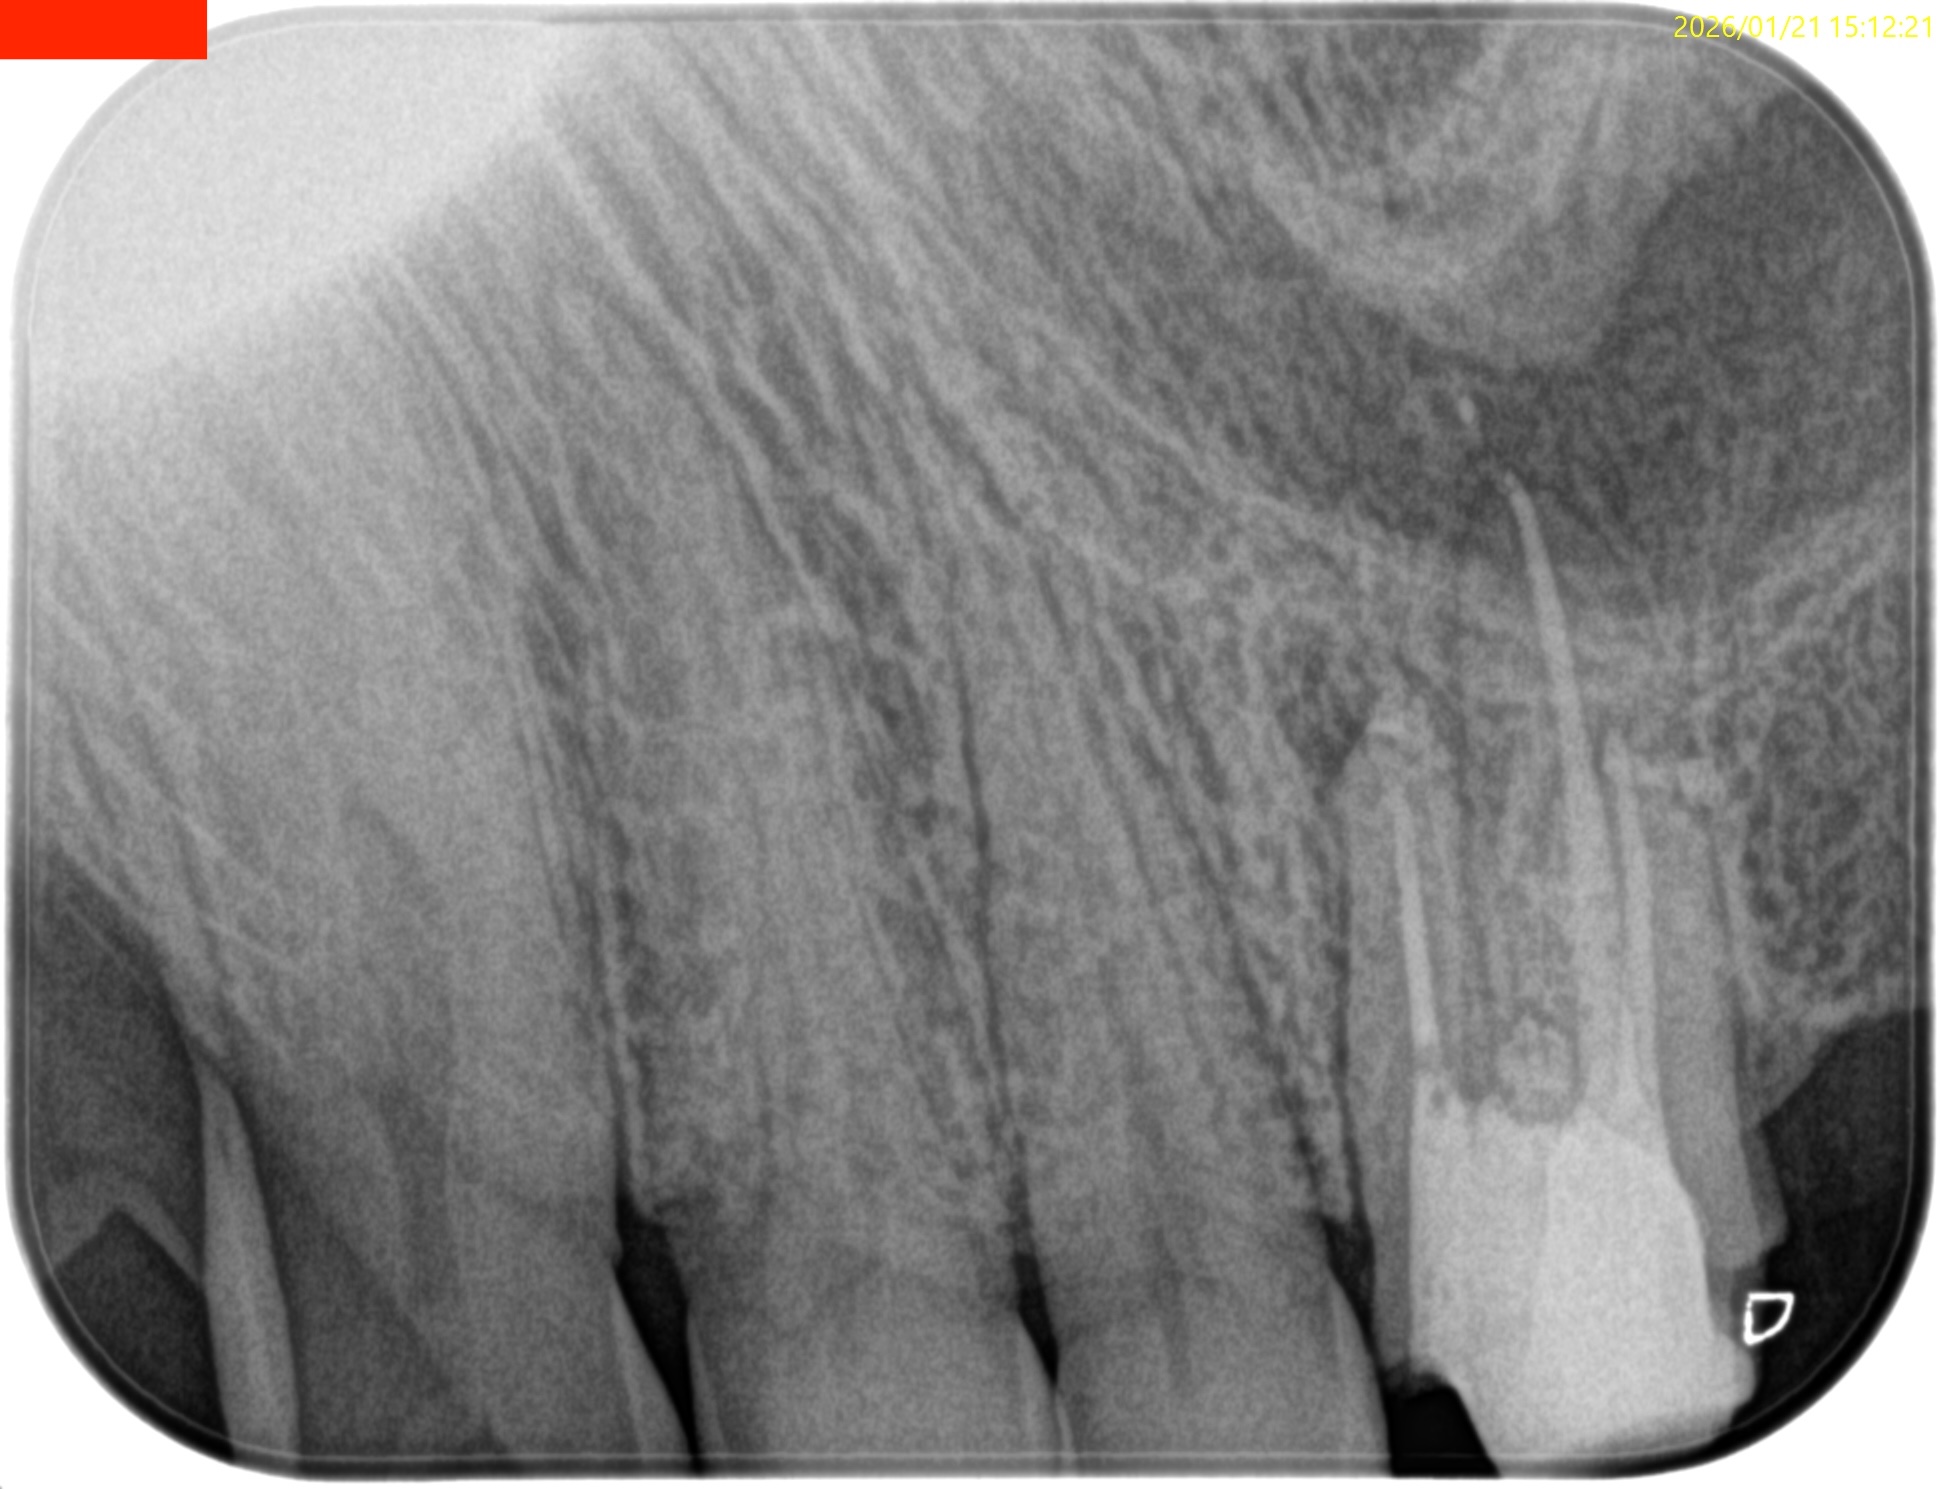

#14 RCT 2yr recall(2026.1.21)

MB1

MB2

DB

P

MB,DBの根尖部に病変が残存している。

臨床検査での咬合痛が生活に支障があるそうだ。